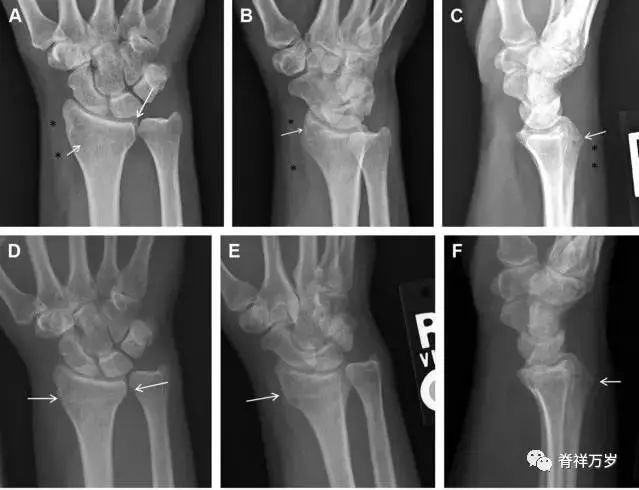

33.腕掌关节骨折脱位

腕掌关节骨折脱位为高能量损伤,常伴有神经损伤。腕掌关节组成骨多,侧位片上重叠遮挡多,骨折不易发现,容易漏诊。在前后位片上,关节面不平滑、关节间隙不对称、关节皮质破坏、关节面重叠常提示腕掌关节骨折脱位。特别是第 4、5 腕掌关节脱位,在前后位片上不容易发现;该损伤不稳定,也称为「变异型拳击手损伤/骨折」。

图 4 第 4、5 腕掌关节骨折脱位。(A)正常腕掌关节,关节面平衡起伏、平行;前后位(B)、斜位(C)、侧位(D),第 5 掌骨近端附近软组织肿胀(白色箭头),冠状面关节面重叠,背侧撞击剪切应力致钩状骨骨折(*),在前后位及斜位片上可见双密度影。第 4 掌骨底部可见微小骨折碎片(D,虚线箭头),第 4、5 掌骨掌侧成角。(E~G)变异型拳击手损伤:第 4、5 掌骨背侧脱位而未见骨折(E,虚线方框),钩状骨有骨折小碎片(F,短虚线箭头),第 4 掌骨基底部关节内骨折(G,长虚线箭头)。